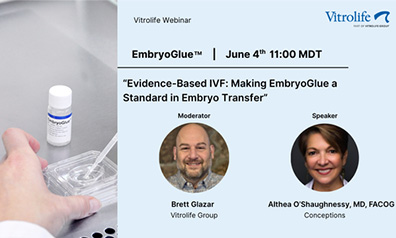

Evidence-Based IVF: Making EmbryoGlue a Standard in Embryo Transfer

This webinar offers a deep dive into EmbryoGlue® , the only embryo transfer medium with a proven impact on implantation and live birth rates. Dr. O'Shaughnessy discusses the science behind hyaluronan-enriched media, clinical outcomes, and how EmbryoGlue supports implantation by mimicking the natural environment of the uterus. This live webinar was held in June 2025.